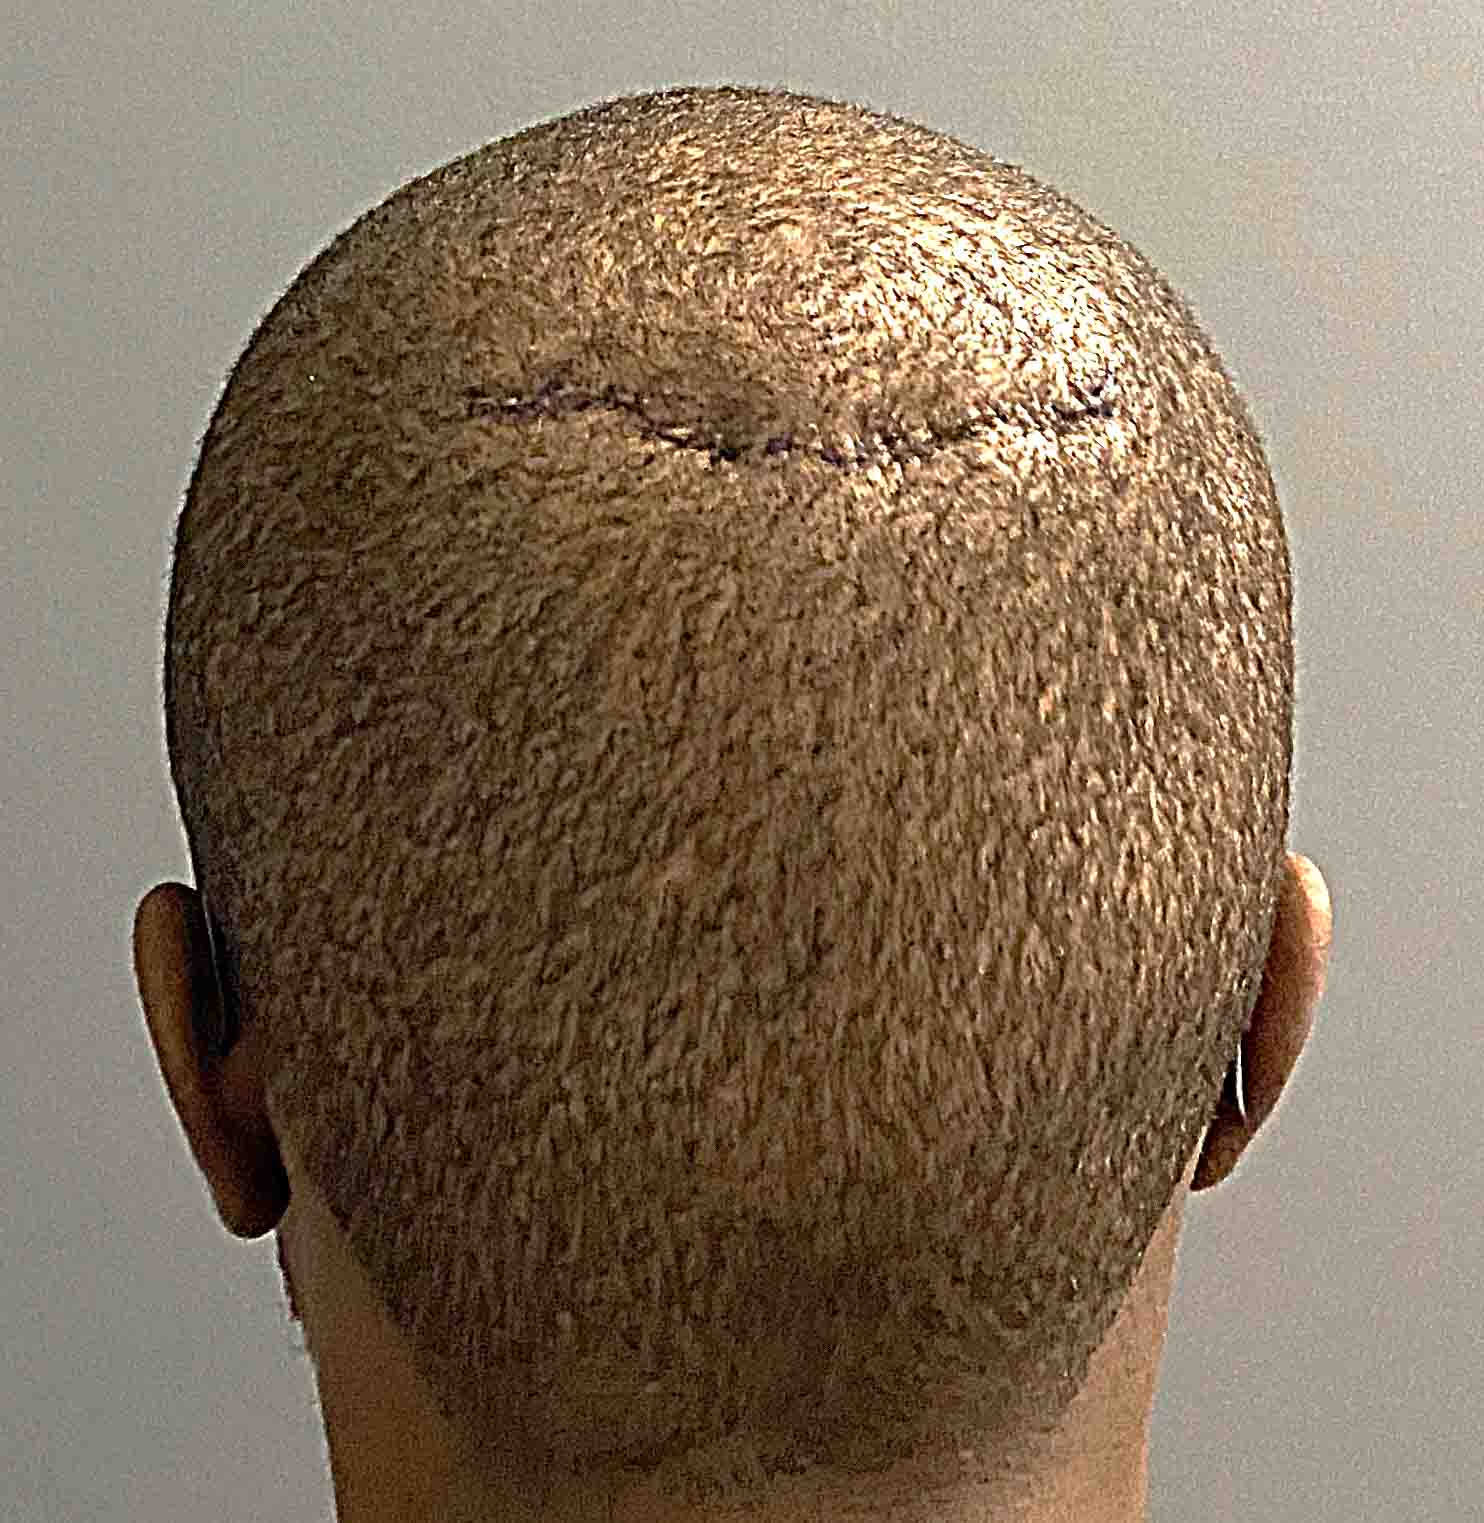

Patient 48

Removal of prominent midline sagittal bony ridge on top of head.

Reduction of posterior sagittal skull ridge through a small 3 cm scalp incision.

Removal of prominent midline sagittal bony ridge on top of head.

Reduction of posterior sagittal skull ridge through a small 3 cm scalp incision.